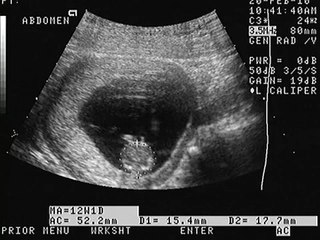

¿En qué ayuda un ultrasonido entre las semanas 11-13.6 del embarazo por un médico materno fetal?